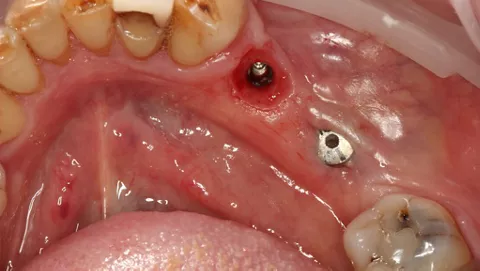

Similarly, at LL6 the implant exhibited insufficient primary stability (< 20 N·cm) and was placed subcrestally with a cover screw for submerged healing, while the mesial implant at LL5 (when stability was adequate > 45 N·cm) received a HealFit® abutment to support soft‑tissue maturation during healing (7.).

7. Distal implant placed with a cover screw, and mesial implant restored with a HealFit® SH anatomical healing abutment.

7

Suturing was adapted to each implant site. The distal implant was fully submerged with a cover screw, requiring complete primary closure. At the mesial implant, where a HealFit® SH abutment was placed, only two simple interrupted sutures were placed mesially and distally to stabilize the soft tissues.

8. Suturing was adapted to each implant site. The distal implant was fully submerged with a cover screw, requiring complete primary closure. At the mesial implant, where a HealFit® SH abutment was placed, only two simple interrupted sutures were placed mesially and distally to stabilize the soft tissues.

8